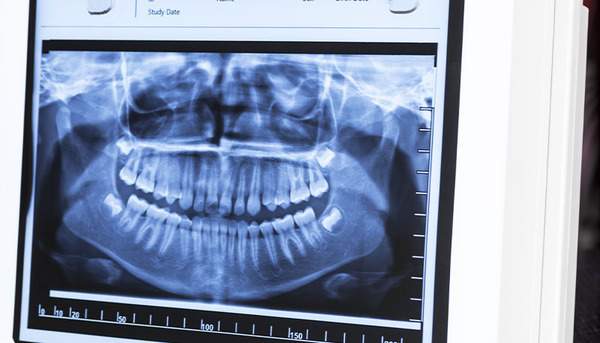

レントゲンについて

歯科治療で使うレントゲンは放射線量がごくわずかで照射する口腔内と腹部は距離があるので、レントゲンをとっても問題ないといわれています。

当院では念の為防護用のエプロンを体につけていただき、撮影を行なっています。

また、当院では必要と考えられる場合に撮影をしますが、もし不安なので撮影したくないといったご要望があればおっしゃってください。

当院のCTはパノラマ写真より低被爆です!